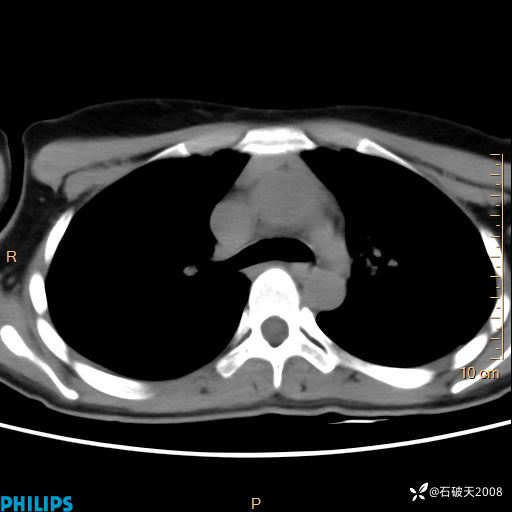

影像诊断要密切结合临床,真的很有必要(病理已公布)

女 21岁 主 诉:发现右侧颈部肿物18年余。

现病史:18年余前患者无明显诱因发现颈部偏右侧有一肿物,具体大小不明确,咳嗽、憋气时肿物增大,局部无疼痛,无吞咽不适,无胸闷及呼吸困难,至当地医院检查考虑良性病变(具体不详)并未做特殊处理,现患者自觉肿物随年龄增长而进一步变大,今日至我院行颈部CT平扫+增强提示:1.右侧颈根部、锁骨上窝及纵隔内异常密度影,考虑良性病变,淋巴管瘤?囊肿?请结合临床。2.双侧颈部小淋巴结。建议结合临床及其他相关检查。现为行进一步治疗,门诊以“颈部局部肿物”为诊断收住我科,发病来患者神志清,精神可,饮食睡眠可,大小便正常,体重无下降。

平扫